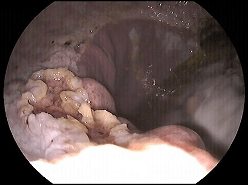

The stomach is full of acid for digestion. For a number of reasons there is a breakdown in the normal protective covering in the stomach allowing the acid to burn into the stomach lining. The below image shows grade 4 gastric ulcers.

Gastric ulcers range from mild areas of inflammation in the horses stomach lining through to erosion of the stomach lining.